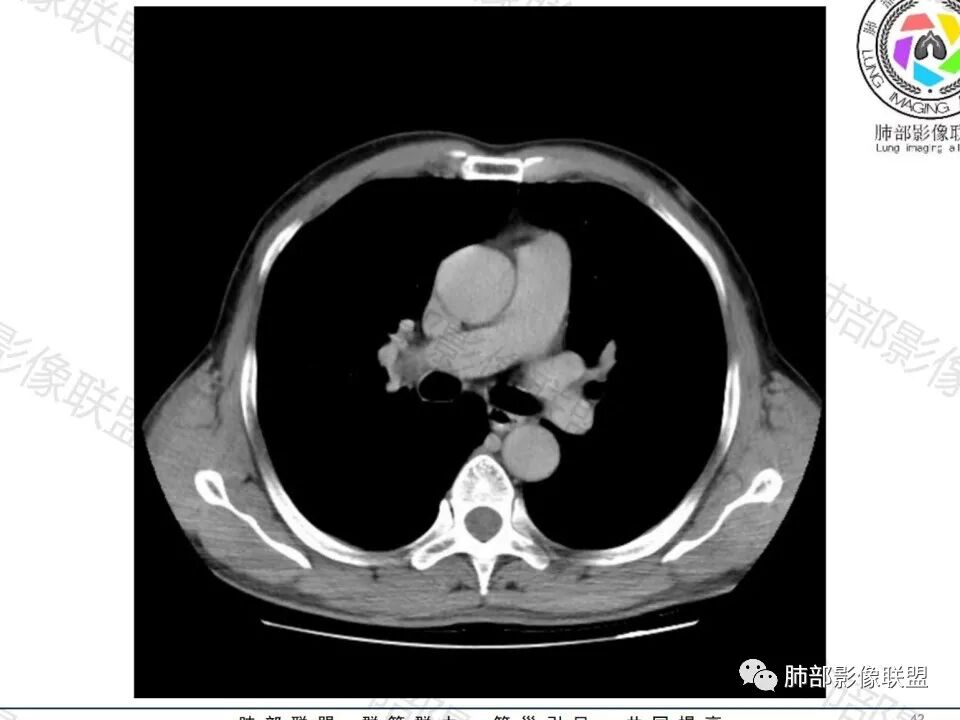

类圆形,边缘稍平直,周围晕中细微毛刺,密度均匀,均匀强化,血管走形自然,稍牵拉扭曲,支气管在近端堵塞

这枚结节的纵隔窗在没有调节窗位的情况下,已经很密实了,说明这个结节里面是软组织的成分,这与普通炎性结节(隐球菌等)的密度还是有区别的,很多年前就有人提出,纵隔窗显示越大,恶性可能越大;

结节周围有磨玻璃影,边界似清不清的,但是总体不如炎性晕征那么模糊;

增强的程度很难讲,但是不均匀强化是可以确定的;

有收缩力,但是很轻,按照常理,实性结节因为有占位效应,不太会有收缩力,但是叶间胸膜有凹陷。所以讲,这个结节还是开了放心。